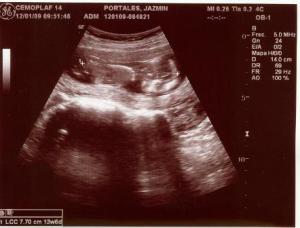

Fotos del 19 En 2009:

Informe:

Embarazo con feto de 13 semanas 4 días +/- 1 semana.

Placenta: Anterior lateral izquierda grado 0

Líquido Anmiótico: Cantidad normal

Impresión: Feto único, vivo con movimientos normales y actividad cardiaca normal. OCI cerrado.

Ovarios normales y fondo de saco de Douglas libre.